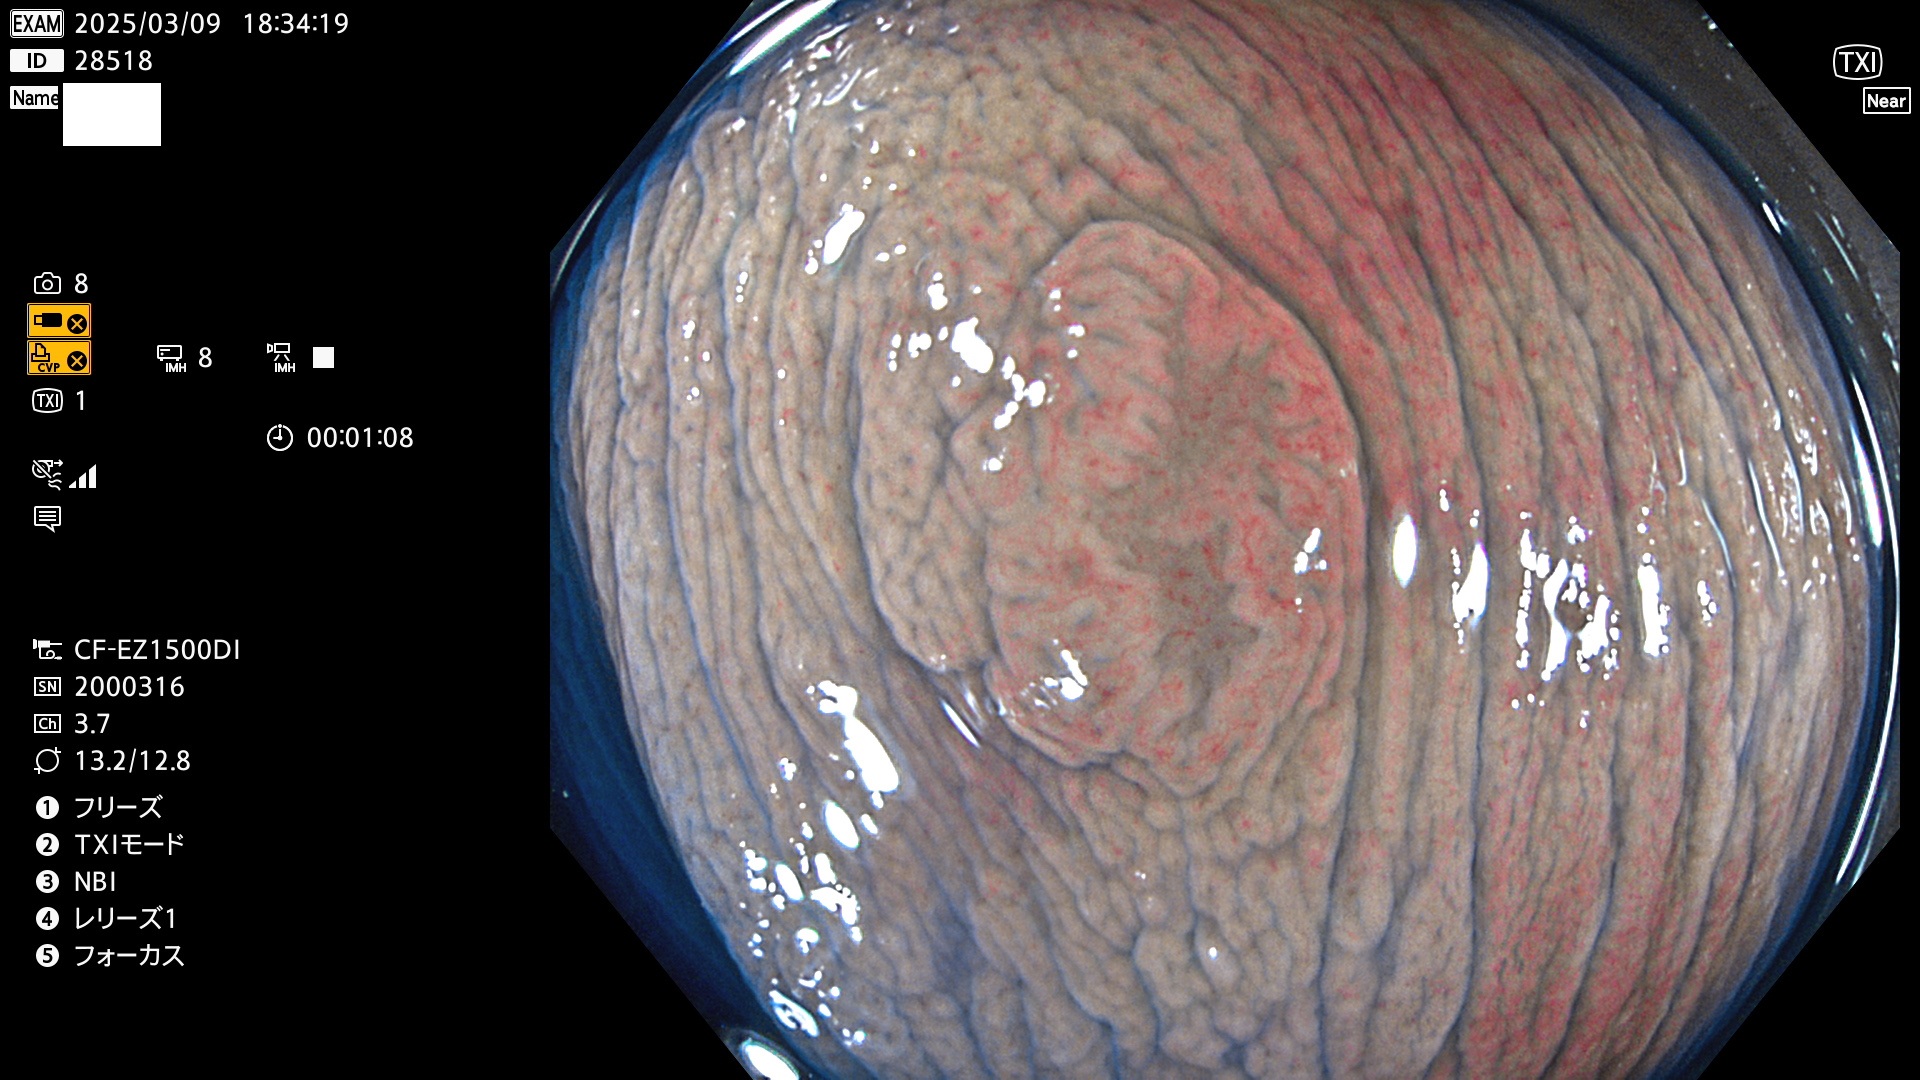

今週のUb、Uc型腺腫

完全に平坦な物をUb、陥凹している物をUcと呼びます。最も発見が難しく危険な病変です。

毎週の検査(木・金・土・日)に発見されたUb、Uc型・腺腫を、その週の日曜の夜にUPし1週間、提示します。

抽出の対象期間 2025年3月6日〜3月9日の4日間(48件の検査)5個 (5/48=10%)